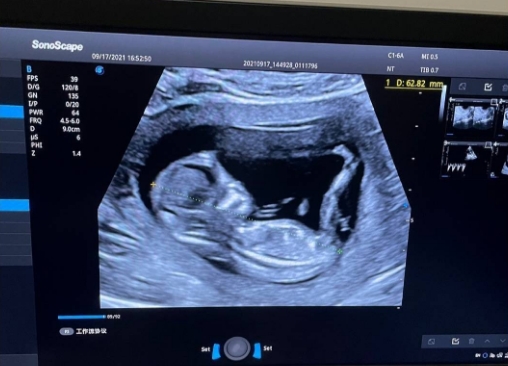

拿到B超报告看到“双顶径8.5厘米”时,不少孕晚期孕妇会心头一紧:“这个数值是不是太小了?生下来会不会体重不足?”其实,双顶径8.5厘米本身没有“大”或“小”的绝对答案——它可能是孕32周胎儿的正常数值,也可能是孕36周胎儿的偏小数,核心判断逻辑是“结合孕周、其他生长指标、胎儿整体发育节奏”综合评估,单靠一个数值下结论既不科学,也容易徒增焦虑。

判断双顶径8.5厘米是否正常,最核心的参考是“检测时的孕周”。在孕32-34周这个阶段,胎儿头部发育速度较快,双顶径达到8.5厘米属于完全正常的范围,说明头部发育与孕周匹配,只要其他指标无异常,无需担心“生下来小”的问题。

临床中判断胎儿大小,依靠的是“头部+躯干+四肢”的多指标组合,而非单一双顶径。头围(HC)比双顶径更全面,能反映胎儿头部整体轮廓,避免因“头型偏扁或偏圆”导致的误判;腹围(AC)是评估胎儿躯干发育的关键,直接关联内脏发育和脂肪储备,腹围正常通常意味着营养供给充足;股骨长(FL)则反映下肢发育情况,与双顶径的比例(一般为0.68-0.72)能判断身体比例是否协调。

除了超声指标,医生还会通过“胎儿估重公式”计算大致体重,公式通常融合双顶径、腹围、股骨长三项数据,结果比单看双顶径精准得多。比如同样是双顶径8.5厘米,若腹围29厘米、股骨长6.5厘米,估重约2400克(孕34周左右正常);若腹围32厘米、股骨长7.0厘米,估重可达2800克(孕36周左右正常),两者对应的“大小”判断完全不同。